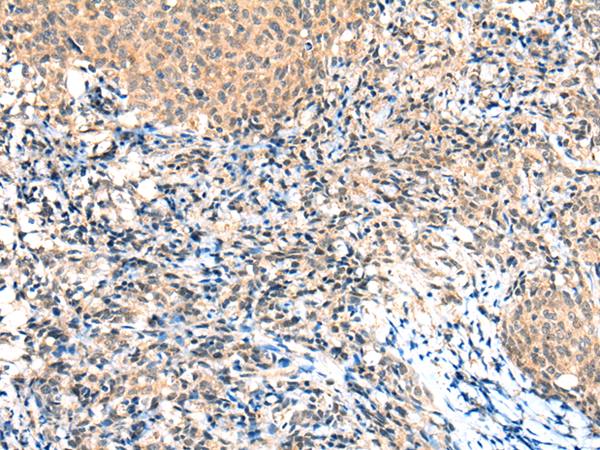

IHC positive control: |

Human cervical cancer |

IHC Recommend dilution: |

25-100 |